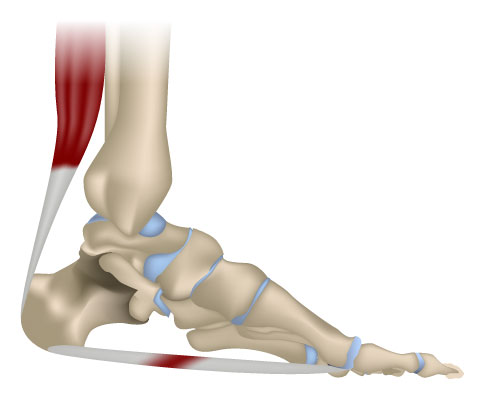

Achillessehnenentzündung (Achillodynie)

Die Achillessehne ist die stärkste Sehne im menschlichen Körper. Sie verbindet den Wadenmuskel mit dem Fersenbein und sorgt für die Kraftübertragung und Dämpfung beim Laufen und Springen. Plötzliche Belastungswechsel reizen die Achillessehne, wodurch sie sich schmerzhaft entzündet. Auch eine Fehlstellung des Fersenbeins kann zu Schmerzen am Ansatzpunkt der Achillessehne führen. Die Kraftwirkung wird dann nicht mehr optimal übertragen. Eine Achillessehnenentzündung kann unbehandelt zur Ruptur (Riss) der Achillessehne führen.

Der Fersensporn gehört zu den Sehnenansatzentzündungen (Tendinopathien). Sowohl der Achillessehnenansatz am Fersenbein (Achillodynie) als auch der Ansatz der großen Sohlenplatte (Plantarsehne) am Fersenbein (unterer Fersensporn) können betroffen sein.

Betroffene leiden unter Fersenschmerzen beim Auftreten, Stehen und Laufen. Der Orthopäde muss differentialdiagnostisch abklären, ob andere Auslöser wie eine Fersenbeinfraktur, eine Schleimbeutelentzündung im Bereich der Achillessehne oder eine Haglundferse vorliegt.